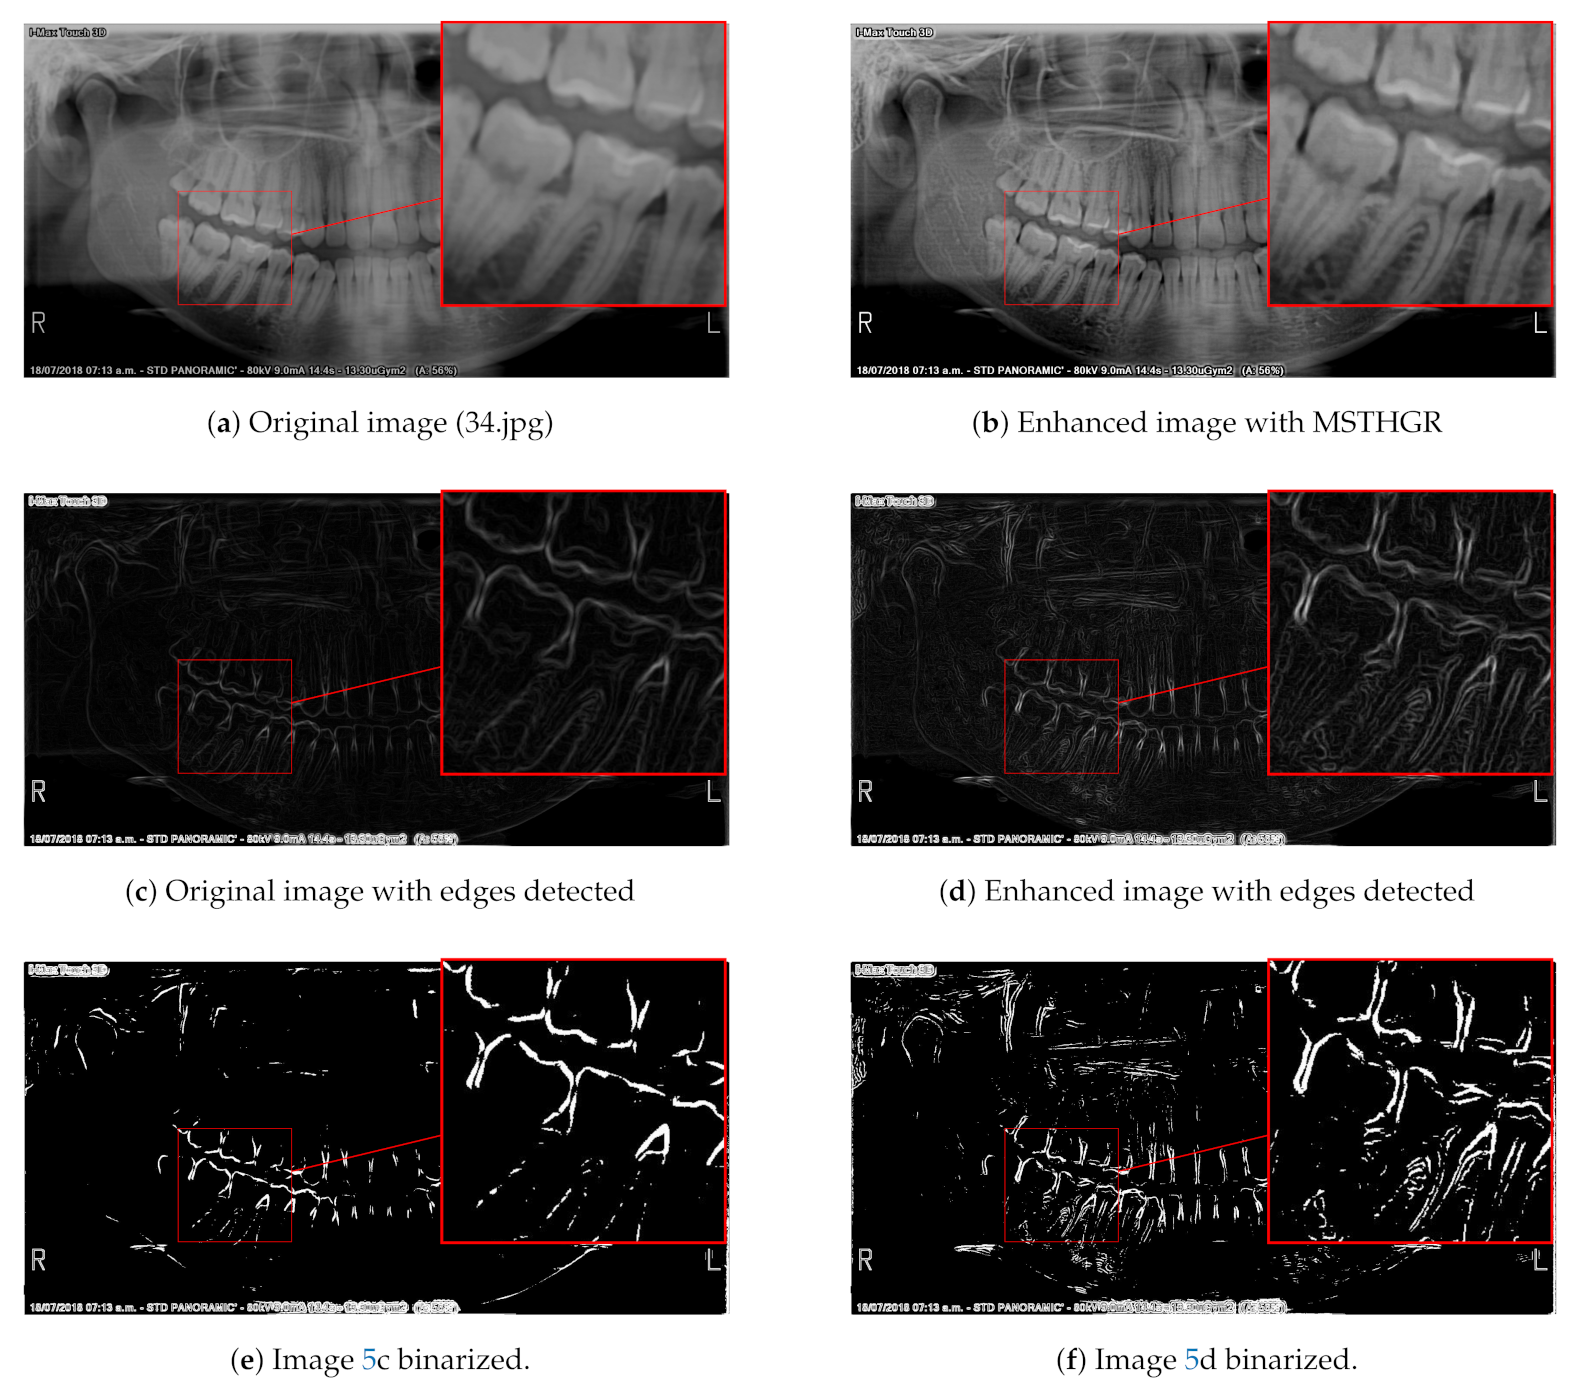

2.3. Edge Detection or Segmentation Application

3.3. Numerical and Visual Results

- For the REC metric, MSTHGR was numerically superior to the GRMMCE, QHELC and GC algorithms.

- For the CIR metric, MSTHGR was numerically superior to the GRMMCE, HE, BBHE, DSIHE, MMBEBHE, QHELC and CLAHE algorithms.

- For the E metric, MSTHGR was numerically superior to the GRMMCE, HE, BBHE, DSIHE, MMBEBHE, QHELC and GC algorithms.

- For the SF metric, MSTHGR was numerically superior to all compared algorithms.